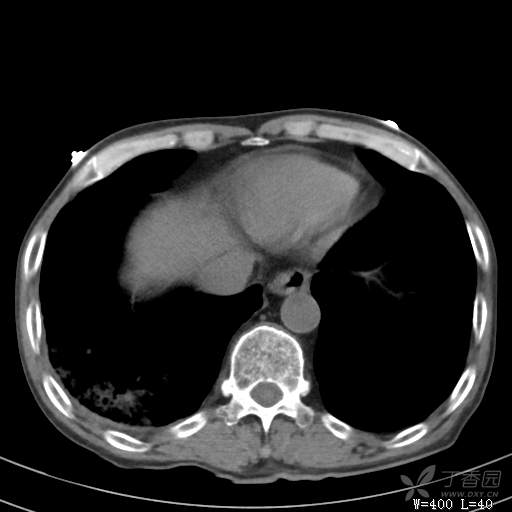

简要病史:主因发热伴腰背部疼痛2小时于2018-06-27,09:30 入院。患者无高血压,冠心病、糖尿病病史,无慢性咳喘史,不吸烟。否认食物药物过敏史。患者于入院前2小时出现发热,体温37.5℃,无咳嗽,咳痰,伴右侧腰背部疼痛,伴呕吐2次,呕吐物为黄绿色胆汁,大便2次,为稀便,无咯血,无胸闷、憋气,无鼻塞、流涕,无尿频、尿急、尿痛,就诊于我院,我院急诊查:上腹部CT:右肾结石,右下肺感染性疾病可考虑,血常规WBC13.54*109/L,GR%45.8%,急诊以“发热待查:肺感染?”收入院。

辅助检查:上腹部CT:右肾结石,右下肺感染性疾病可考虑,血常规:WBC13.54*109/L,GR%45.8%,。心肌酶示:谷草转氨酶12U/L,乳酸脱氢酶328U/L,肌酸激酶20U/L,肌酸激酶同工酶7U/L,α-羟丁酸脱氢酶277U/L,查凝血常规示:凝血酶原时间12.5秒,国际标准化比值1.07,活化部分凝血酶原时间32.6秒,纤维蛋白原浓度1.77g/L,凝血酶时间15.6秒。

临床诊断:1.腰背部疼痛原因待查:1.肺炎?2.泌尿系结石?。